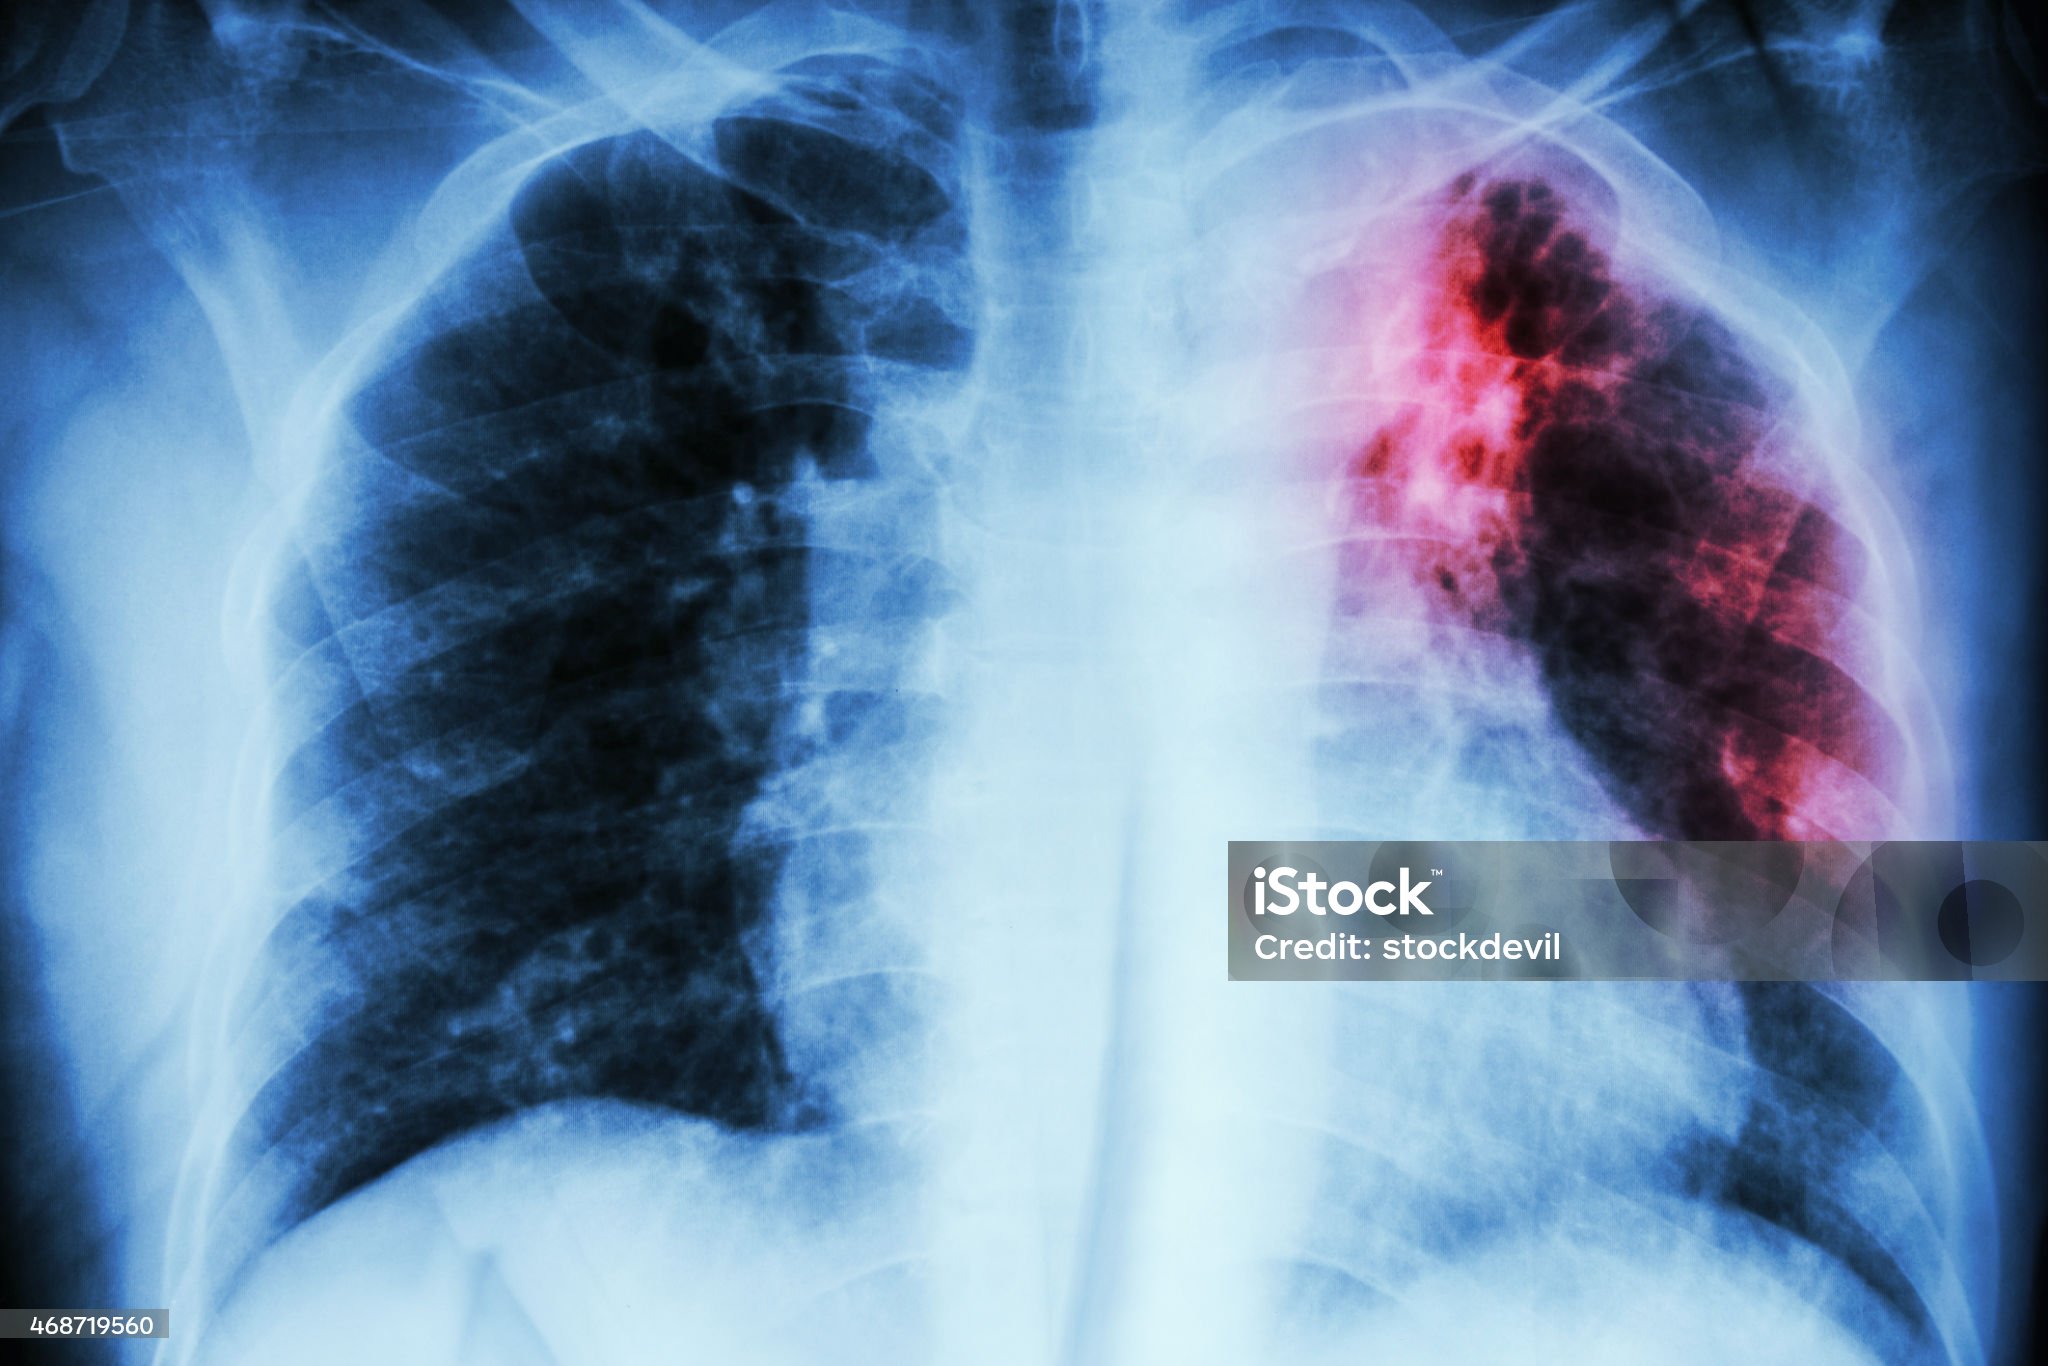

결핵은 특히 ‘3주 이상’ 마른기침이 계속되는 것을 대표적인 초기 증상으로 꼽습니다. 초기에 약간의 불편감이나 목 가려움 정도로 시작하지만, 점점 기침 횟수가 잦아지고 목소리가 쉬거나 흉통까지 동반될 수 있습니다. 특히 아침에 기침이 심하거나, 활동할 때 증상이 심해진다면 결핵의 가능성이 높아집니다. 기침이 오래간다고 무조건 결핵은 아니지만, 지속되는 기침이 있다면 반드시 병원에서 흉부 엑스레이 또는 객담검사(가래 검사)를 통해 확인하는 것이 안전합니다.

결핵은 초기에 치료하면 완치가 가능하지만, 방치할 경우 폐 손상, 전신 감염 등 심각한 후유증으로 이어질 수 있습니다. 특히 면역력이 약한 노약자, 당뇨나 만성질환을 가진 사람은 감기 증상이 오래 지속되면 결핵 검사를 포함한 정밀검사를 고려해야 합니다. 일반 기침은 자연 회복되는 경우가 대부분이지만, 결핵은 반드시 의학적인 진단과 치료가 필요한 질환이라는 점을 명심해야 합니다.